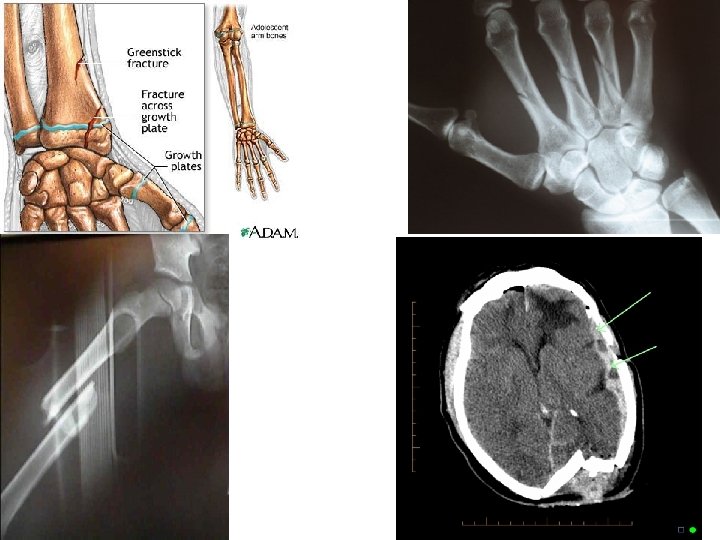

Endochondral Bone Development • Most bones start out as hyaline cartilage models. • Primary Ossification center: Middle of bone/diaphysis 1. Periosteum develops allowing blood vessels to pentrate. 2. Cartilage cells change into osteoblasts and begin to deposit bone. • Secondary ossification centers at epiphyses. • Epiphyseal line formed from the epiphyseal plate when ossification centers meet. Growth of long bone stops when they meet.

Epiphyseal Plate

How Do Bones Repair After a Fracture? Fracture: A break in a bone.

Fractures

Bone Repair a) Blood escapes and forms a hematoma. b) Chrondrocytes fill gap with fibrocartilage. Soft callus is formed. c) Spongy bone is deposited by osteoblasts. (Bony callus formed. ) d) Bone remodeling occurs: Osteoclasts will remove excess bone of callus and reconstruct shaft walls until remodeled area looks resembles original unbroken region.